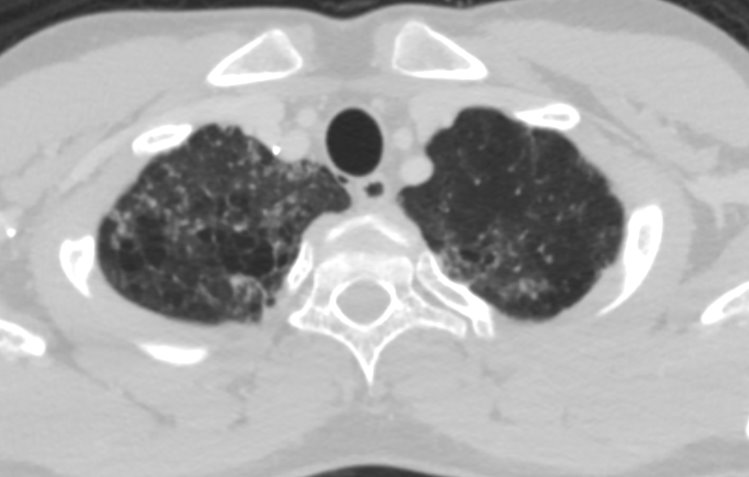

View Case48 year old male Presented with history of 3 episodes of melena. No known comorbidities Gastro -Duodenoscopy - Erosive duodenitis Colonoscopy – unremarkable.

48 year old male Presented with history of 3 episodes of melena. No known comorbidities Gastro -Duodenoscopy -Erosive duodenitis Colonoscopy – unremarkable.